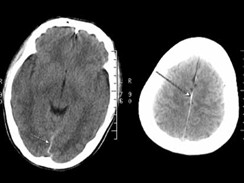

脑CT扫描或MRI检查:临床疑诊SAH首选CT检查,安全、敏感,并可早期诊断。出血当天敏感性高,可检出90%以上的SAH,显示大脑外侧裂池、前纵裂池、鞍上池、桥小脑角池、环池和后纵裂池高密度出血征象,并可确定脑内出血或脑室出血,伴脑积水或脑梗死,可对病情进行动态观察。CT增强可发现大多数动静脉畸形和大的动脉瘤。MRI可检出脑干小动静脉畸形,但须注意SAH急性期MRI检查可能诱发再出血。CT可显示约15%的患者仅中脑环池少量出血,称非动脉瘤性SAH(non aneurysmal SAH,nA—SAH)。